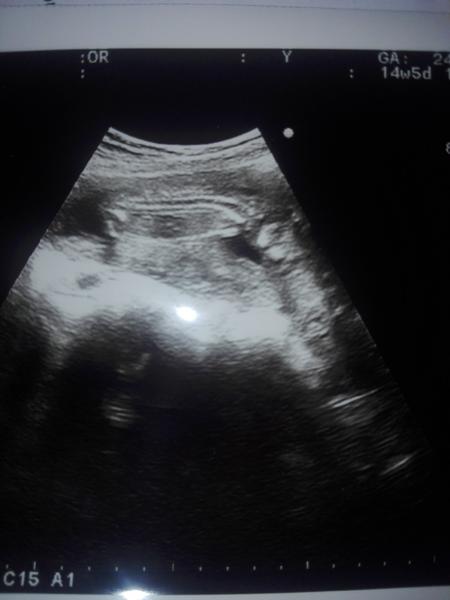

Bude to dievka alebo chlapček?

Baby co si myslite je to chlapcek ci dievka?myslim ze tam vidim pipika ale moze to byt aj susurka a pupocna snura...co myslite vy?

@wejka333 ja mám takýto UTZ snímok pri dcére, v ktorom si tt?

15 🙂 a myslis teda ze ta palicka moze byt pupocnik ano?posli foto ak mozes utz tvojej dcerky na porovnanie 🙂

je tam podľa mňa vidieť kávové zrno, fakt neviem v ktorom albume mám snímok, ale je podobný😉

Vsak presne, s tohoto uhlu sa to urcit neda v tomto tyzdni. Lepsie sono a iny pohlad treba, lekar nic nepovedal?

Baby tak dnes som bola na kontrole a vraj je to dievka pravdepodobne tak dufam se to aj tak ostane klop klop 🙂 inaac tripple testy vysli dobree na downa 1:52000 a na razstep 1: 60000 tak sme spokojny 🙂